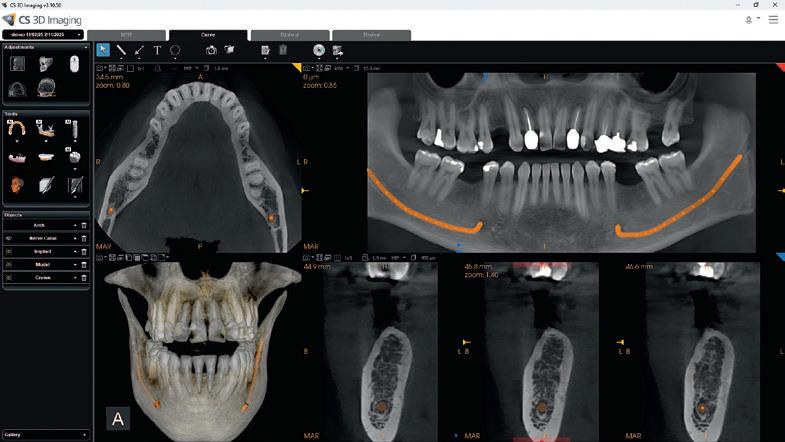

Digital imaging systems now utilise 2D and 3D radiography in ways that mean the transfer of patient information is incredibly quick and simple. The use of

dedicated scanning centres can therefore thrive. Where some practices do not have immediate access to advanced solutions, they may be able to refer a patient to a scanning centre, or another practice with the appropriate equipment, before treating them back in the practice once they have received the imaging results. This community of interconnected dental professionals can work together to support larger patient bases, and be confined less by in-practice equipment.

Access to different solutions ensures patients can get the types of scans that are suited to their care. A cone beam computed tomography (CBCT) scanner and a conventional computed tomography (CT) scanner offer different advantages. If a clinician requires greater detail in the soft tissue, a CT scan would be effective, but if this can be forgone for a lower radiation dose at a higher resolution, a CBCT scan may be more ideal – dental professionals could refer appropriately.

Sensei Cloud from Sensei, the practice and patient management brand of Carestream Dental, helps clinicians step into a world of interconnected dental care. Dental professionals can use the cloud-based system to manage 24/7 online bookings and patient communications with ease, as well as real-time dashboards for business data. All information is GDPR compliant and secured with state-of-the-art cybersecurity tools, to ensure patients are protected.